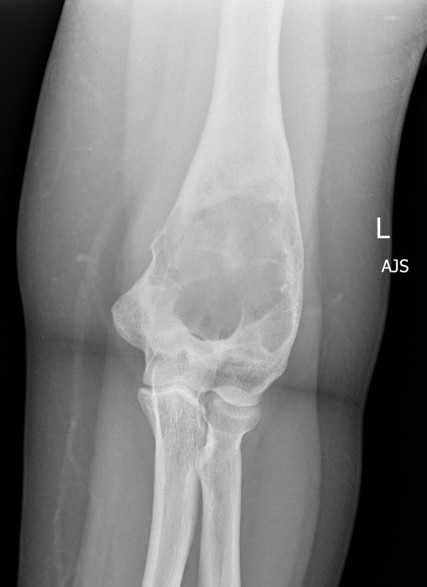

Long bones

- pathological fracture

- deformity / bowing

Craniofacial involvment

- slow growing painless masses

- cosmetic deformity / dental problems / vision and hearing loss

X-ray

Intramedullary lucent diaphyseal lesion with 'ground glass appearance'

- thinned, slightly bulged cortex

- ± endosteal scalloping

- may have angular deformity / bowing